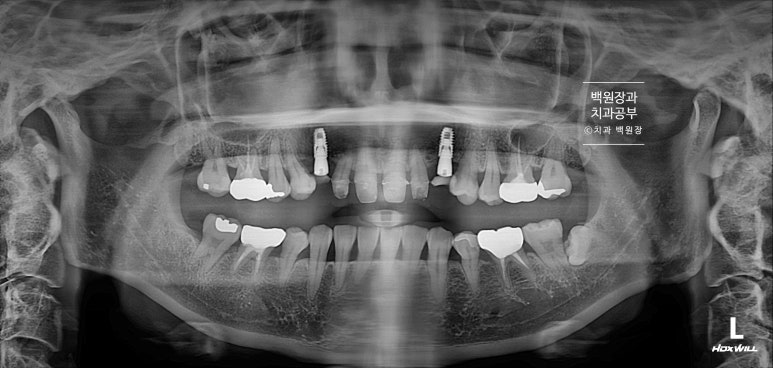

파노라마 엑스레이에서 확실히 확인할 수 있는데요,

똑같이 6개의 앞니를 별로 표시해 보았습니다.

빨간색으로 표시한 두 개의 송곳니 모두 치근우식이 있는 것을 관찰할 수 있습니다. 뿌리에 충치가 심했어요.

노란색 화살표로 가리킨 곳에 파노라마 엑스레이상 소견으로 까맣게 충치가 생겨있는 것을 볼 수 있죠.

치료 완료 후 치과용 파노라마 엑스레이 사진입니다!

아주 깔끔하게 6개의 크라운이 잘 제작되어 있는 것을 보실 수 있을거에요.

치료 전 후를 비교해보면, 여섯개의 크라운이 따로 제작되어 모두 떨어져 있는 형태를 가지고 있고 두개의 임플란트는 아주 가지런한 방향으로 잘 수술되어 있는 것을 보실 수 있을겁니다.